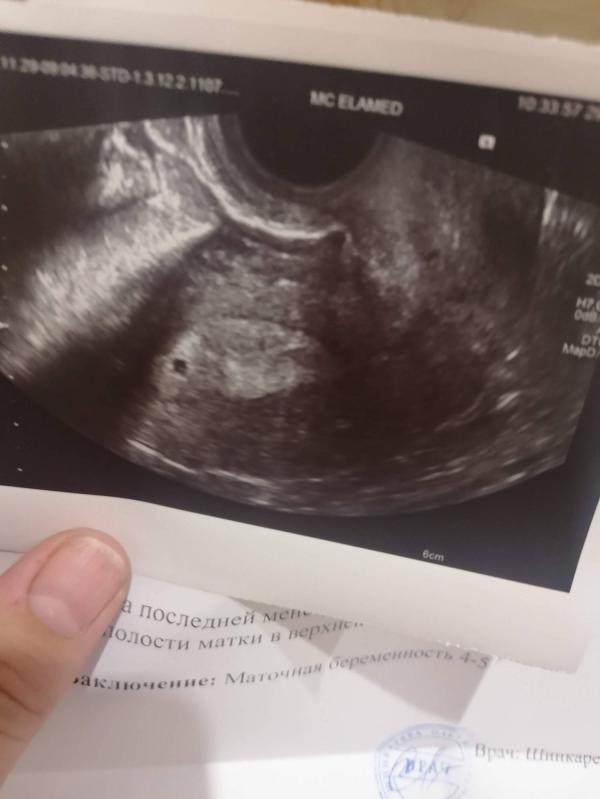

В начале ноября я попадаю к молодому, скорее всего неопытному,врачу. Он посмотрел меня и озвучивает что овуляции опять нет, желтое тело совсем маленькое и беременность не наступит. Он предлагает мне пробовать после года подать по квоте на ЭКО. Я принимаю эту ситуацию и решаю ждать марта и начать сбор документов. Но в конце ноября, я как всегда покупаю тест и он показывает 1 полоску, я кладу его в шкаф в туалет и еду к другу на день рождения. По приезду смотрю на этот тест и какой-то блик второй полоски. На сл. День я покупаю второй тест и там их две. Я думаю, что это чудо, ведь недавно сказали беременность не наступит. Через неделю я записалась на узи и там подтвердили да маточная беременность 4 недели. Вы можете себе представить мои чувства? Я была на седьмом небе от счастья. Через две недели я еду слушать сердцебиение и там мне говорят, что наверное рано сердца не слышно пока и говорят приехать через неделю. Я приезжаю опять и снова пусто. Еще неделя и пустота. Я ни чего не понимаю, но надеюсь, что все будет хорошо. Но в один день начинается мазня и тут до меня доходит, что это плохо. Я еду в стационар, капают Транексам и дают Дюфастон. Отпускают на выходные домой и в понедельник явка. Если сердца так и нет то чистка..